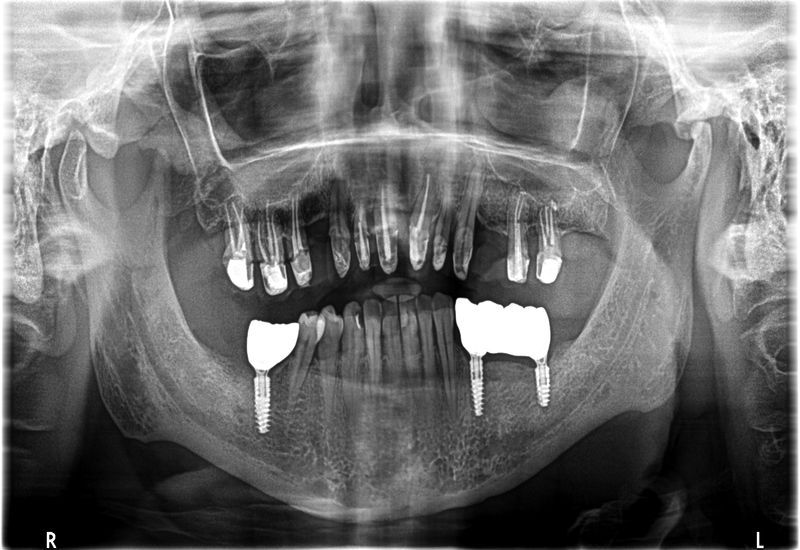

Inny przykład leczenia

Nieleczona choroba przyzębia może niestety prowadzić do utraty zębów. Clinica al Denti to zespół lekarzy zajmujących się wszystkimi dziedzinami stomatologii. Już po pierwszej wizycie jesteśmy w stanie zaproponować Państwu rozwiązanie umożliwiające odbudowę braków zębów nawet bardzo trudnych przypadkach, wymagających usunięcia zębów.